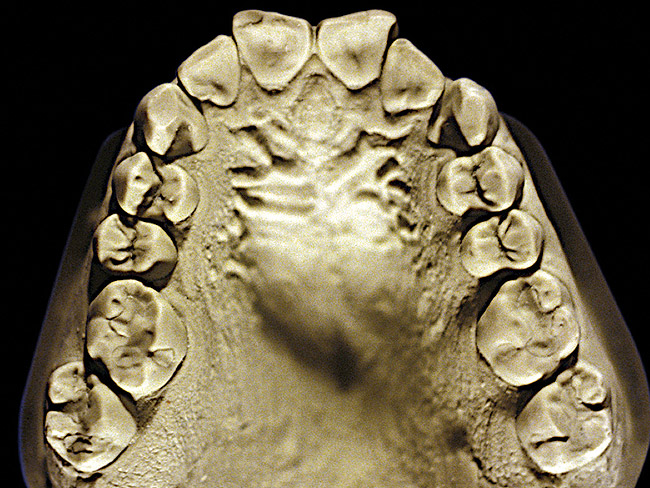

Figure 4  Advanced NCLTS from bruxism, maxillary arch.

Figure 4

The patient shown in Figure 3 and Figure 4 exhibited severe NCLTS from bruxism. Examination of the casts indicated that the NCLTS was progressively greater toward the anterior teeth. Cupping and cratering was not present because there was no secondary cause. Figure 5 and Figure 6 detail another bruxism patient, but to a lesser degree and one with cupping/cratering caused by toothpaste. The cups or craters were not caused from bruxism because the teeth could not touch the bottom of the invaginations. In both featured patients, upon hand-articulating the casts, the NCLTS facets matched up and the diagnosis of bruxism was confirmed.